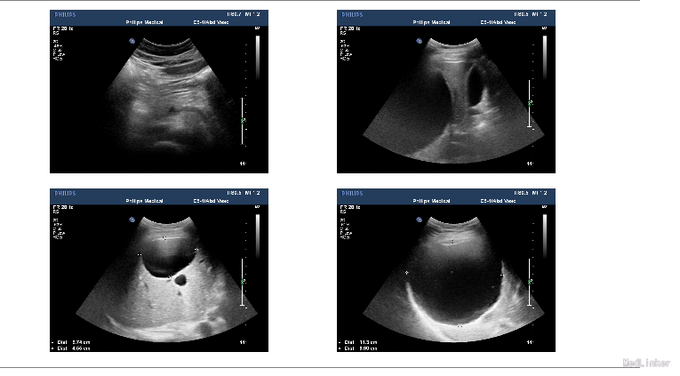

肝囊肿

患者,男,54岁,因“体检发现肝囊肿5年”入院。

外院肝胆B超:肝多发囊肿,肝内脂质沉积。

初步诊断: 肝囊肿.在全麻下行腹腔镜下右肝囊肿开窗术,手术顺利,术后予头孢米诺抗炎治疗及对症支持治疗。患者现术后恢复好,已排便,手术切口愈合好,未及红肿渗出。